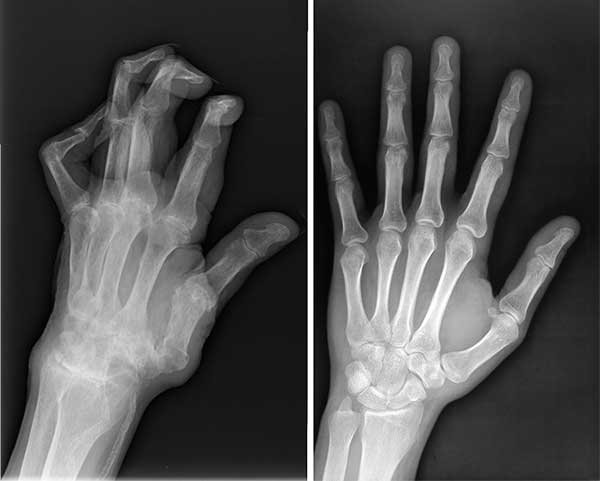

ไม่ใช่แค่หนูคนเดียวที่รอดเพราะผลิตภัณฑ์มหัศจรรย์ตัวนี้ สามีหนูป่วยเป็นโรคข้ออักเสบ ปลายนิ้วเสียหายมาก หนูเลยซื้อ Artiflex ให้เขาทาน พวกเราทานด้วยกันแล้วก็หายกันทั้งคู่เลยค่ะ

ภาพเอกซเรย์เปรียบเทียบก่อนและหลังทาน Artiflex ของสามี

ภาพเปรียบเทียบสภาพมือของสามีก่อนและหลังทาน Artiflex